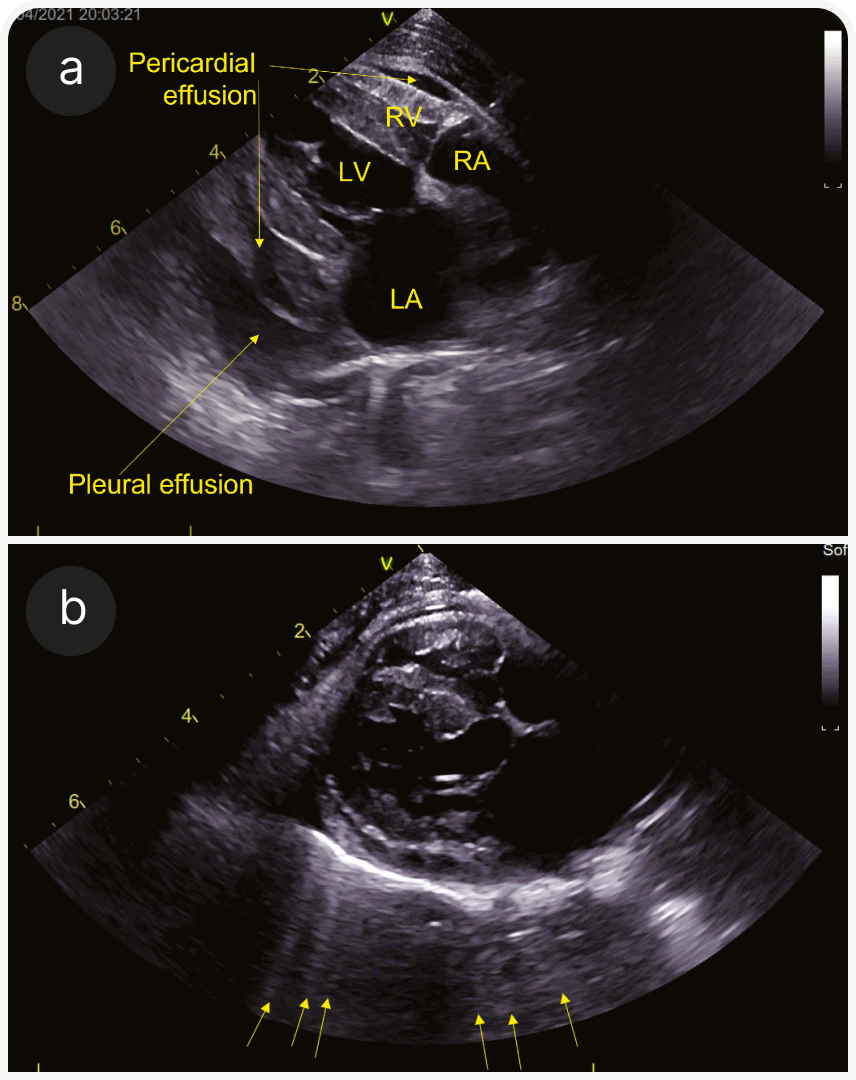

(а) Парастернальная четырехкамерная проекция справа (RPS) по длинной оси; визуализируются плевральный (pleural effusion) и небольшой перикардиальный выпот (pericardial effusion). Левое предсердие субъективно расширено.

(b) Четырехкамерная проекция справа (RPS) по длинной оси; видны B-линии за границей перикард-легкие (стрелки). Это гиперэхогенные радиальные линии, проходящие через легочную ткань; они показывают смесь воздуха и жидкости в легочной паренхиме. Их также можно оценить на УЗИ легких вне тени сердца. На этом изображении левое предсердие субъективно расширено.